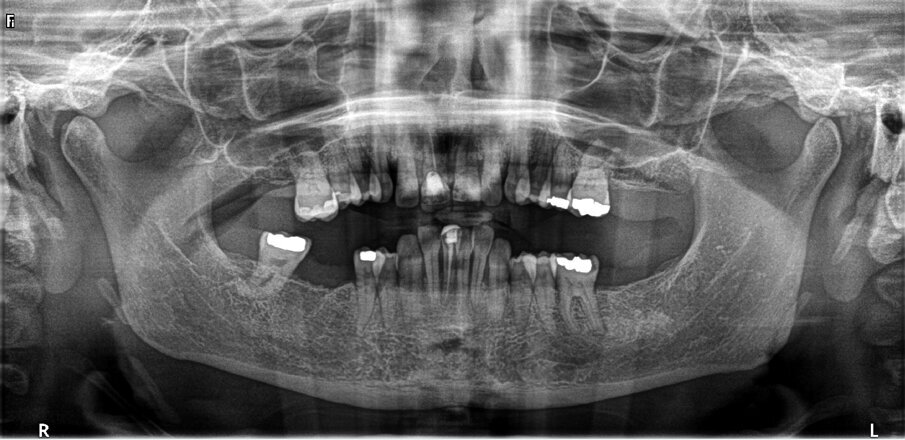

A CBCT scan and panoramic radiograph using the CS 8100 3D device (Carestream Dental; Fig. 3) were taken to accurately capture the information needed to properly plan the treatment for this case that would ensure the most ideal outcome, especially since the patient had discussed how unhappy she was with her existing smile. Using the CS 3D imaging software (Carestream Dental), dental implants were virtually planned in key positions in both arches (Fig. 4).

Fig. 3: Pre-op panoramic radiograph